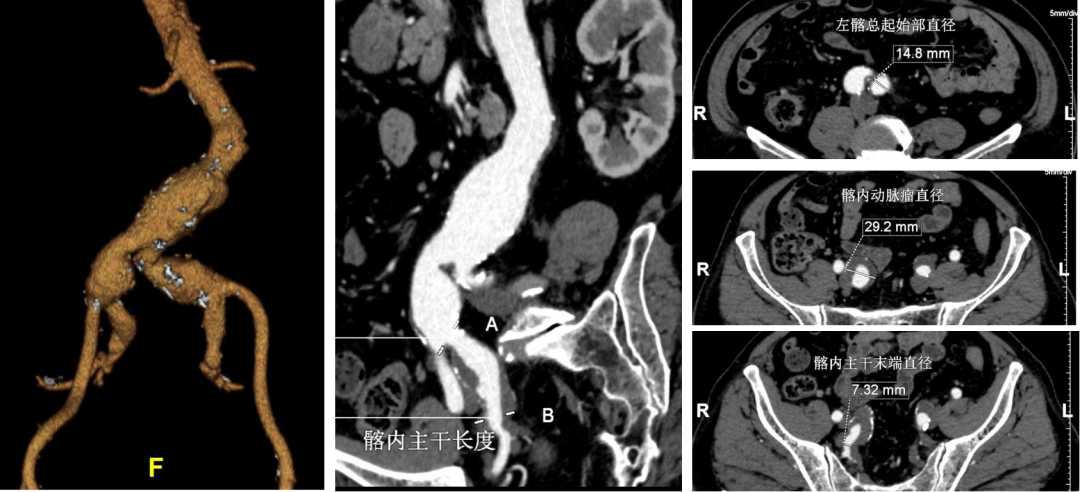

病情:患者男,71岁,双侧髂总动脉并左侧髂内动脉瘤,左侧髂总动脉起始部向右侧严重折曲,担心支架耐弯折性。

策略与操作:双侧差异化重建,右侧髂内动脉主干植入IBE支架;左侧髂内动脉壁支植入G-iliac™支架,通过右股入路配合可调弯导管超选至迂曲段。

右侧IBE,左侧IBD(经右股入路,可调弯导管与12F戈尔长鞘配合进入G-iliac及左侧髂内)

随访结果:术后2年CTA:左侧髂内动脉壁支支架通畅,折曲部位无狭窄或断裂,验证G-iliac™支架的柔顺性与耐久性。